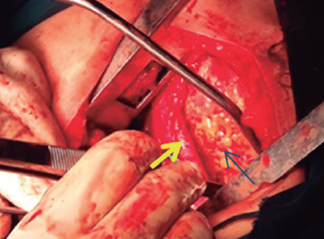

Imágenes y Cirugía

Mauricio Gonzalez-Urquijo